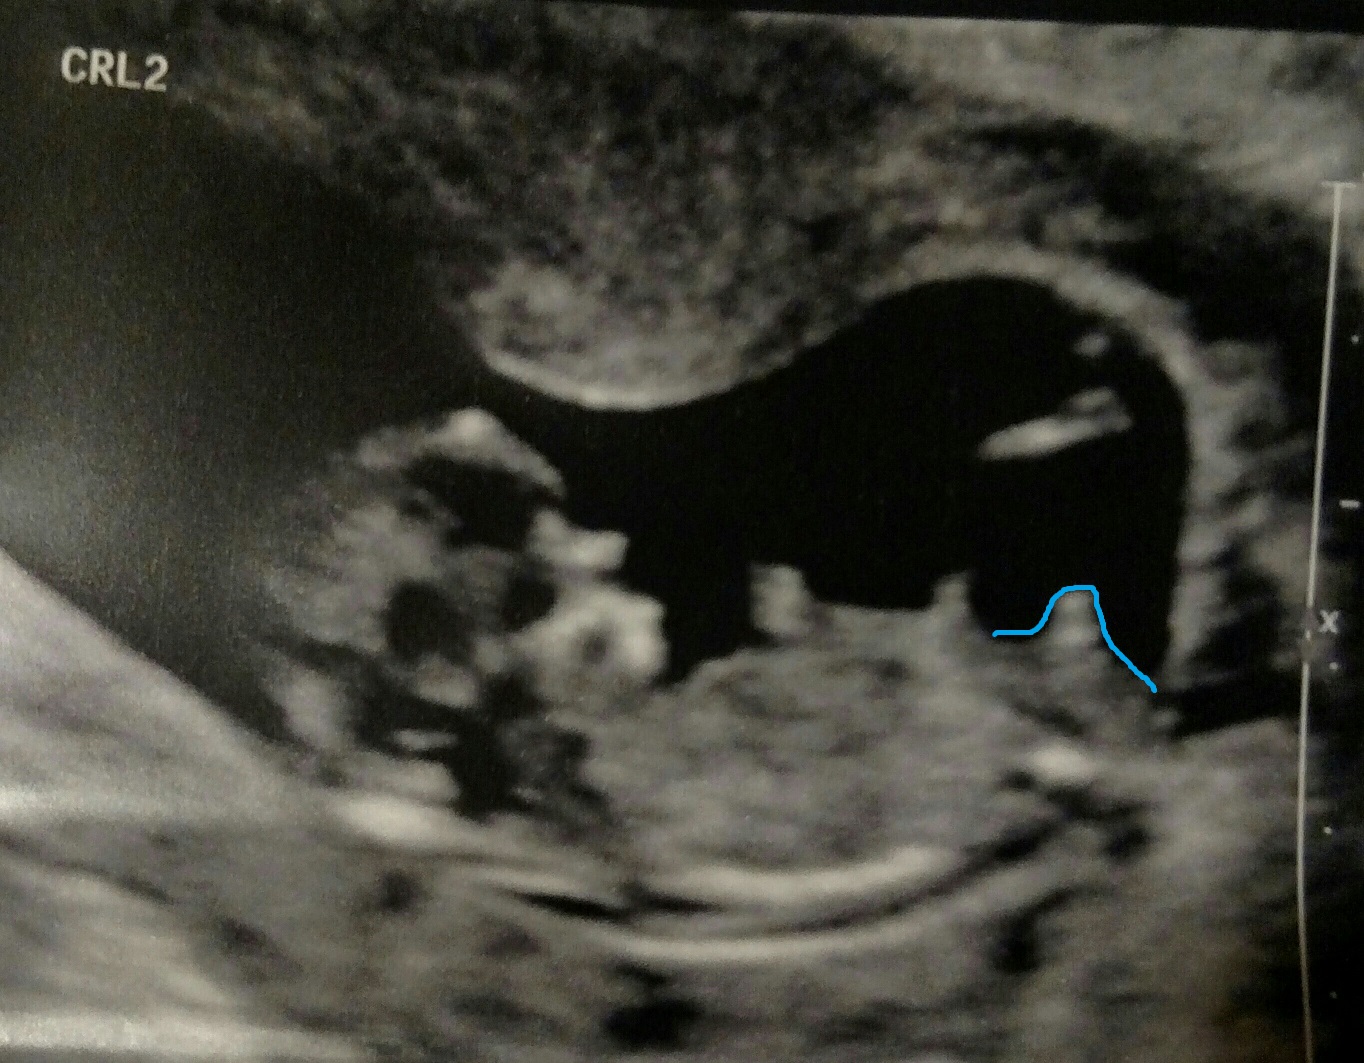

Hey everybody! We just had our 2 week appointment and got to see our little one again. I'm curious as to what you all think about the little one's nub... Boy or girl? Let me know what you think!

Attachment 35277